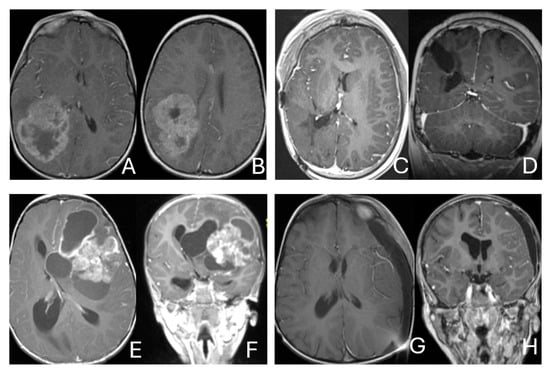

Figure 2.

Multi-lobe ATRT. (A–D): A 3-year-old boy with a heterogeneous frontotemporal ATRT with encasement of Sylvian vessels on MR images ((A), axial; (B), coronal). Intraoperatively, the tumor replaced both the frontal and temporal opercula, extended to the anterior, and displaced/encased branches of the middle cerebral artery. Postoperative MR images after resection ((C), axial; (D), coronal) confirm multilobe involvements. (E–H): of a 30-month-old boy with a temporoparietal cystic ATRT crossing the Sylvian fissure shown on T2-weighted MR images ((E), axial; (F), coronal). Correlative intraoperative findings and imaging demonstrated the tumor extending from the temporal lobe into the posterior frontal lobe across the Sylvian fissure and encasing middle cerebral artery branch. Post-resection MR images ((G), axial; (H), coronal) show a resection cavity spanning the temporal and posterior frontal opercula.